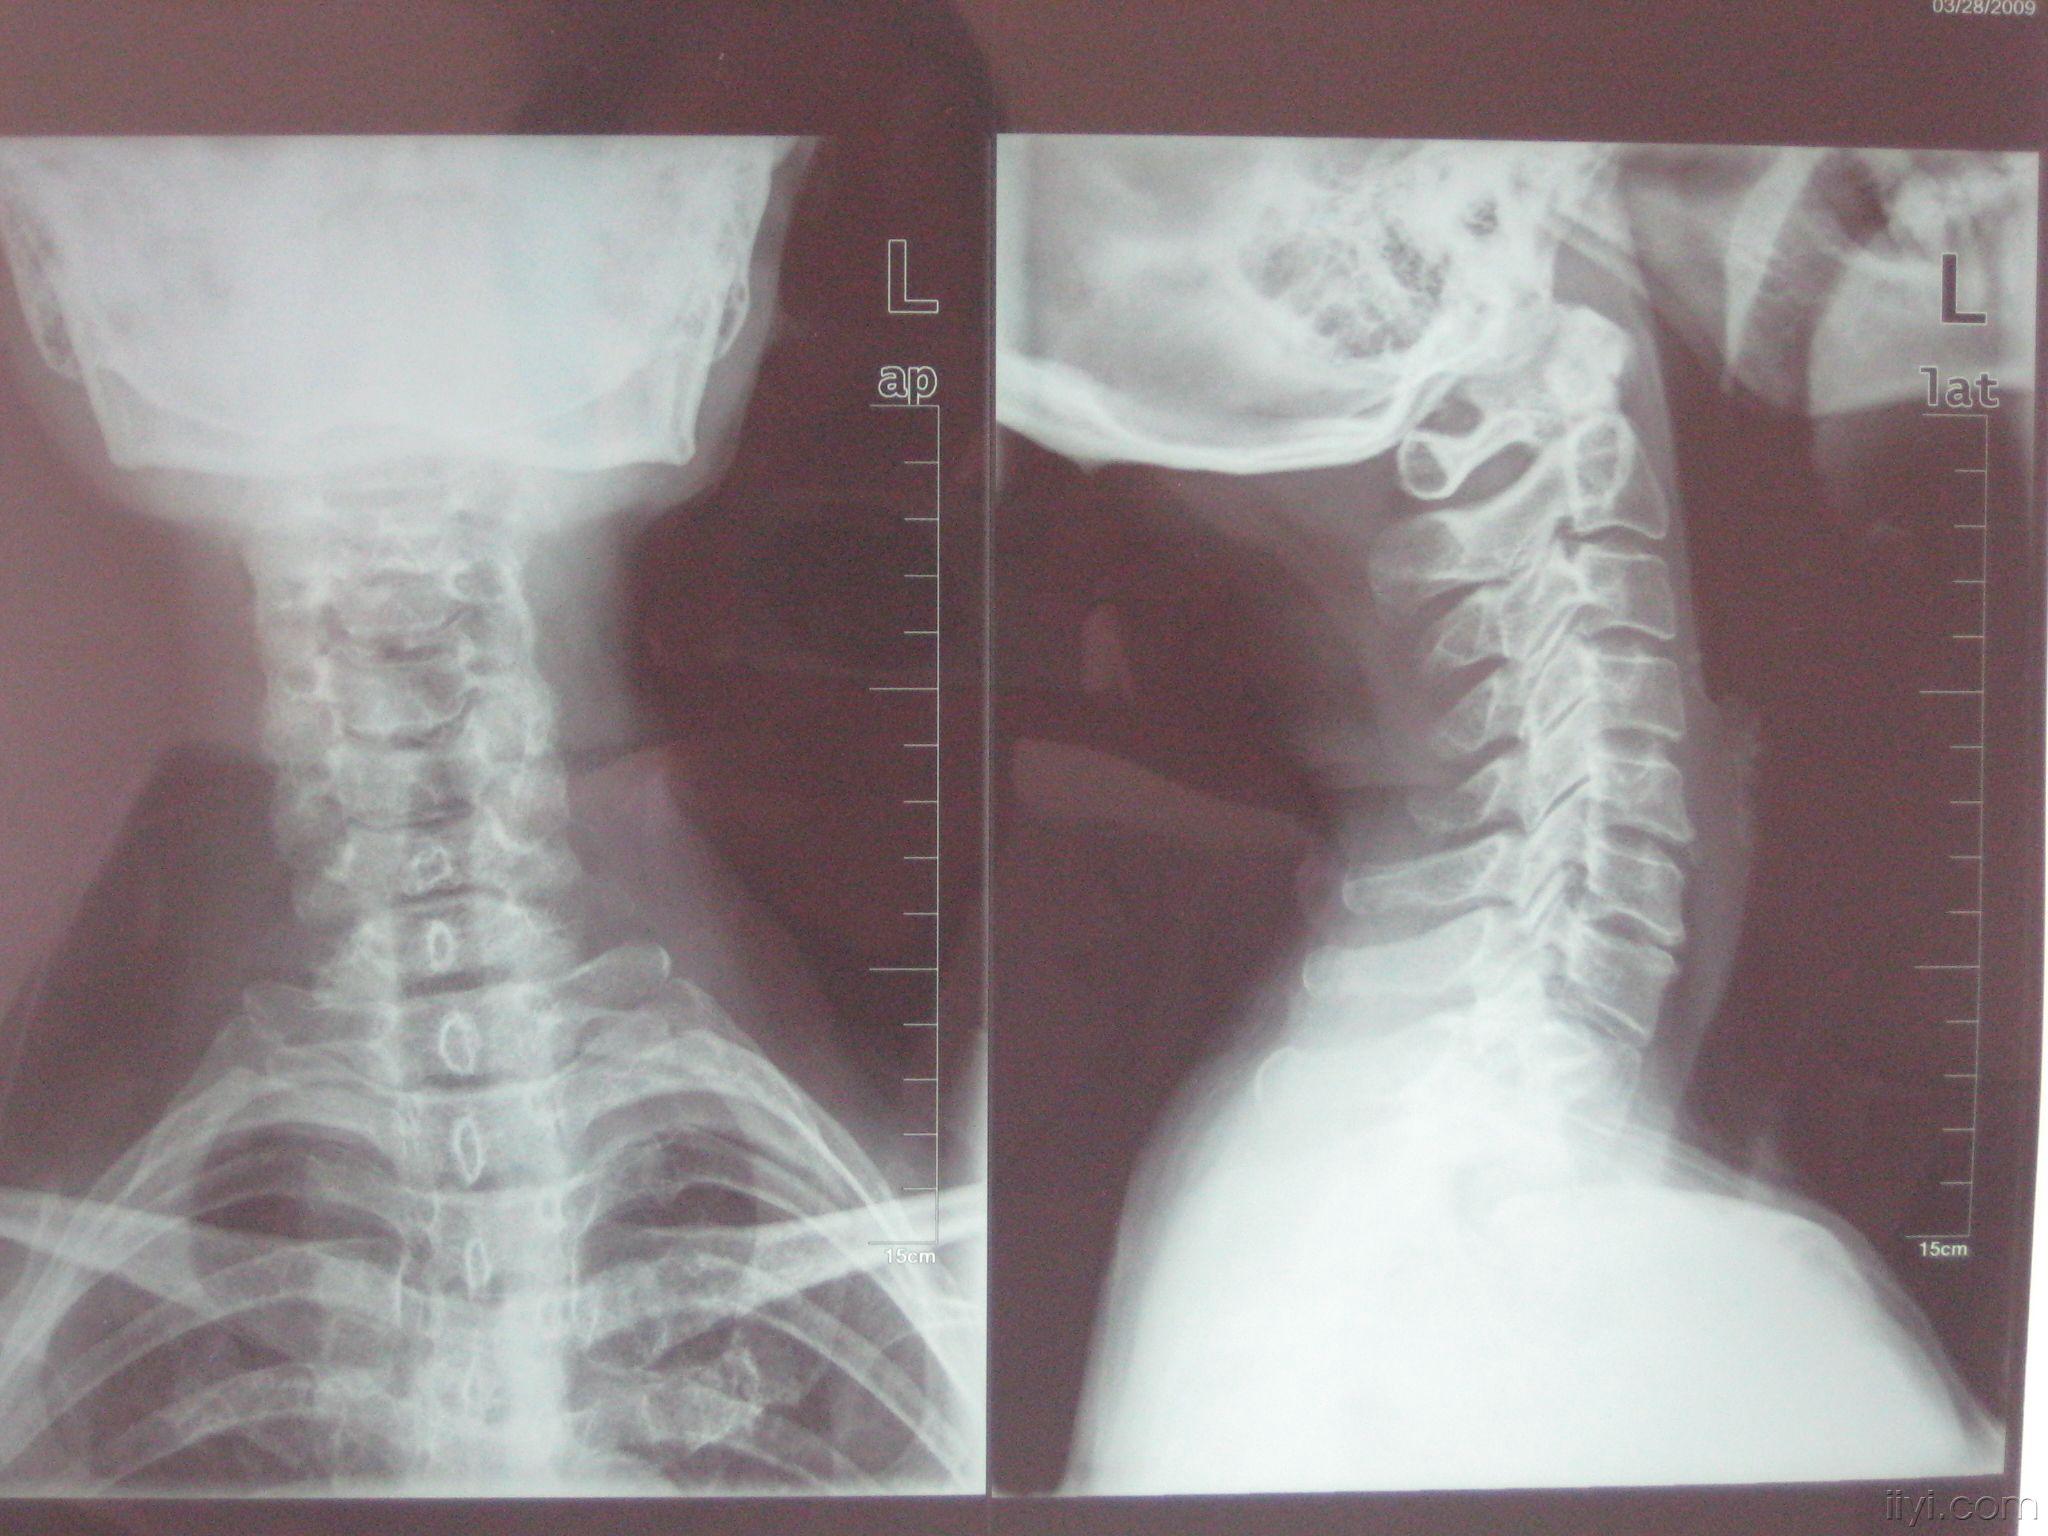

颈椎x片正常

颈椎x片正常,

颈椎x片求助有没问题

颈椎x光?

辅助检查:血常规一;尿常规一;心电图一 附颈椎ct,x片 请诸位爱友讨论

欢迎大家进来讨论这例颈椎病

林夏薇社交网站发现,在六月份的时候,林夏薇曾上载过一张颈椎的x光片